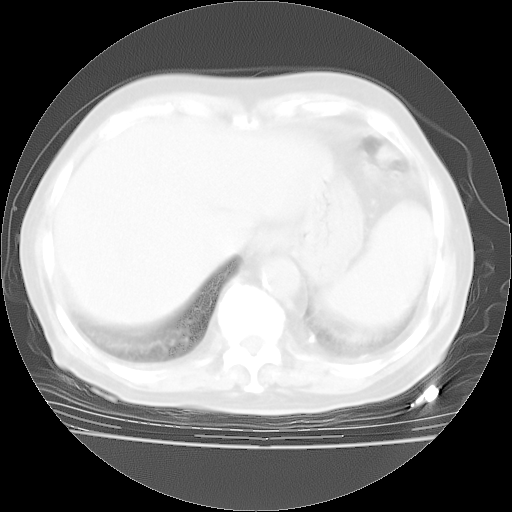

个人阅读4.14日肺部CT平扫:纵隔窗无异常,但肺窗示:双下肺内、后基底段有片絮状侵润影,部位以后基底段为著,以间质改变为主,呈急性肺泡炎征像,和首次住院影像学有相似之处。仅是个人读片,明日请相关专家再读片哈。其它建议同上。

1、108#的是4月14日的胸部CT(发此贴时还没看着28日的CT)。14日的胸部CT其实已经出现改变(如108#所述),个人认为28日的胸部CT除纵膈窗疑似有双侧胸膜增厚或少量胸积液(可行胸部B超明确)外,与4月14日对照病变有所加重;2、已经给予“异烟肼、利福平、乙胺丁醇”抗痨治疗?如果是,甲强龙80mg可缓慢减量;如果环磷酰胺已停用,暂不使用;3、中性粒细胞92%,明显升高,目前体温情况?注意合并细菌感染可能,使用左氧氟沙星情况下,是否联用B-内酰胺类抗菌药物?另外是查免疫全套非风湿全套。

今请临免主任会诊后认为:4月14日胸部CT已有双下肺间质性改变。患者病情复发多系激素减量过快不正规所致。目前甲强龙80mg/日,一周后酌情开始减量,不易过快。环磷酰胺若已停用,暂不使用。他同意目前抗菌药物使用,但应考虑是否加用B-内酰胺类抗菌药物(中性细胞明显增高);2、结核复发目前依据不足;3、若免疫全套各项指标正常,考虑多系特发性肺间质炎可能大。4、加强支持,并注意保护胃黏膜。

今上午去请教了临免、呼吸主任:1、介绍病史和阅读系列胸部CT一致认为:患者肺结核不考虑,仍为肺间质纤维化,目前处于急性肺泡炎阶段。2、若仍发热,可将甲强龙增至:80mg Bid静滴,同时鉴于中性增高,合并细菌感染可能,继续左氧氟沙星治疗,再联用B-内酰胺抗菌药物,如头孢哌酮--舒巴坦;3、停用抗痨药;4、目前甲强龙每日剂量160mg ,体温正常后再酌情减量;目前暂不用免疫抑制剂;4、不建议使用免疫增强剂等;5、加强支持治疗,鼓励患者进食;5、注意随访肝、肾功及血常规情况;6、因患者目前激素用量较大,加用胃黏膜保护剂,防止消化道出血可能。